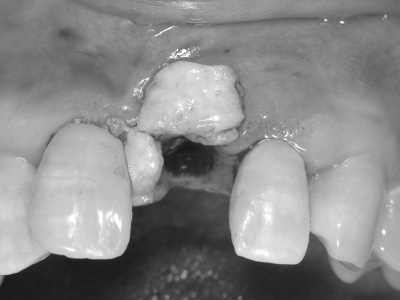

インプラントは骨の中に入るようにできるだけ細いものを使用していますが、それでも骨造成は必要です。

この時点では、歯と歯の間の「歯間乳頭」と呼ばれる歯茎が不足しているため隙間が空いており、インプラントの被せ物がいかにも人工物のように感じるため、審美的な仕上がりとはいえない。

インプラント周りに骨造成も実施しました。